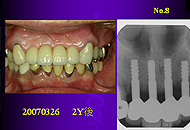

下顎前歯部以外に植立した直径3mm症例はIAI 研究会第9回学術大会で発表した2006年8月までの3年間で、20症例47本であった。

発表に際して直径3mm症例の安全な植立と補綴法をしっかり考察したこともあり、その後この1年間で、さらに21症例50本が追加され、2003年から下顎前歯部以外に植立した直径3mmAQBは計41症例97本となっている。いくら下顎前歯部は欠損しにくい部位であるといっても、同じ時期に下顎前歯部に植立した3mmAQBが5症例7本であるから、私は直径3mmAQBを下顎前歯部以外に植立し始めてから、適応症が大きく拡大したことになる。